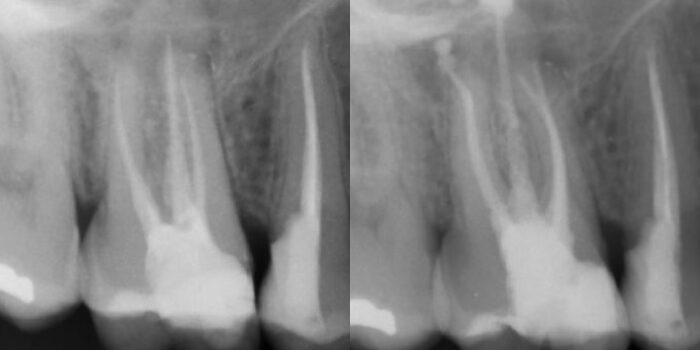

Radiografías finales del caso

Por último, se realiza la reconstrucción definitiva del caso y la radiografía final postoperatoria. Se hará revisión del caso en 6 meses para ver evolución de la lesión apical.